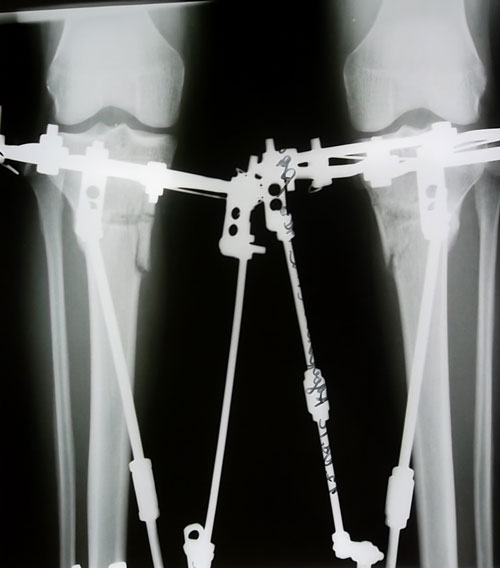

Дата операции 25.06.2012г.ИСХОДНИК.

Моя левая нога изначально была кривее и ее никак не могли выровнять она либо на Х уходила либо на О, 5 дней назад кажется, ну в общем я надеюсь нашли золотую серединку, ещё мешал отек правой ноги. Делала снимки на 20 день, покрутили левую назад, т.к. на Х, на второй день покрутили на натяжение, сегодня т.е. на 29-ый день сделала ещё один снимок, и по нему мне сказали что оси ровные, трогать больше не будут и сделали перемонтаж аппаратов.

Привет. Сегодня у меня 65 дней в аппаратах, чувствую себя хорошо, вовсю хожу, могу садиться и вставать без рук, но иногда по привычке опираюсь, когда лежу ноги закидываю как хочу, без лишних усилий. 27.08. делала снимок, Н.Н. сказал, что снимут аппараты в 2 месяца и три недели, жду не дождусь, устала ходить в аппаратах, хотя они беспокойства не вызывают, просто хочется одеть штанишки, пойти на работу, погулять, прошвырнуться по магазинам... в общем жить полноценной жизнью не вызывая недоуменных, порой обеспокоенных взглядов своей походкой (до сих пор раскачиваюсь при ходьбе).